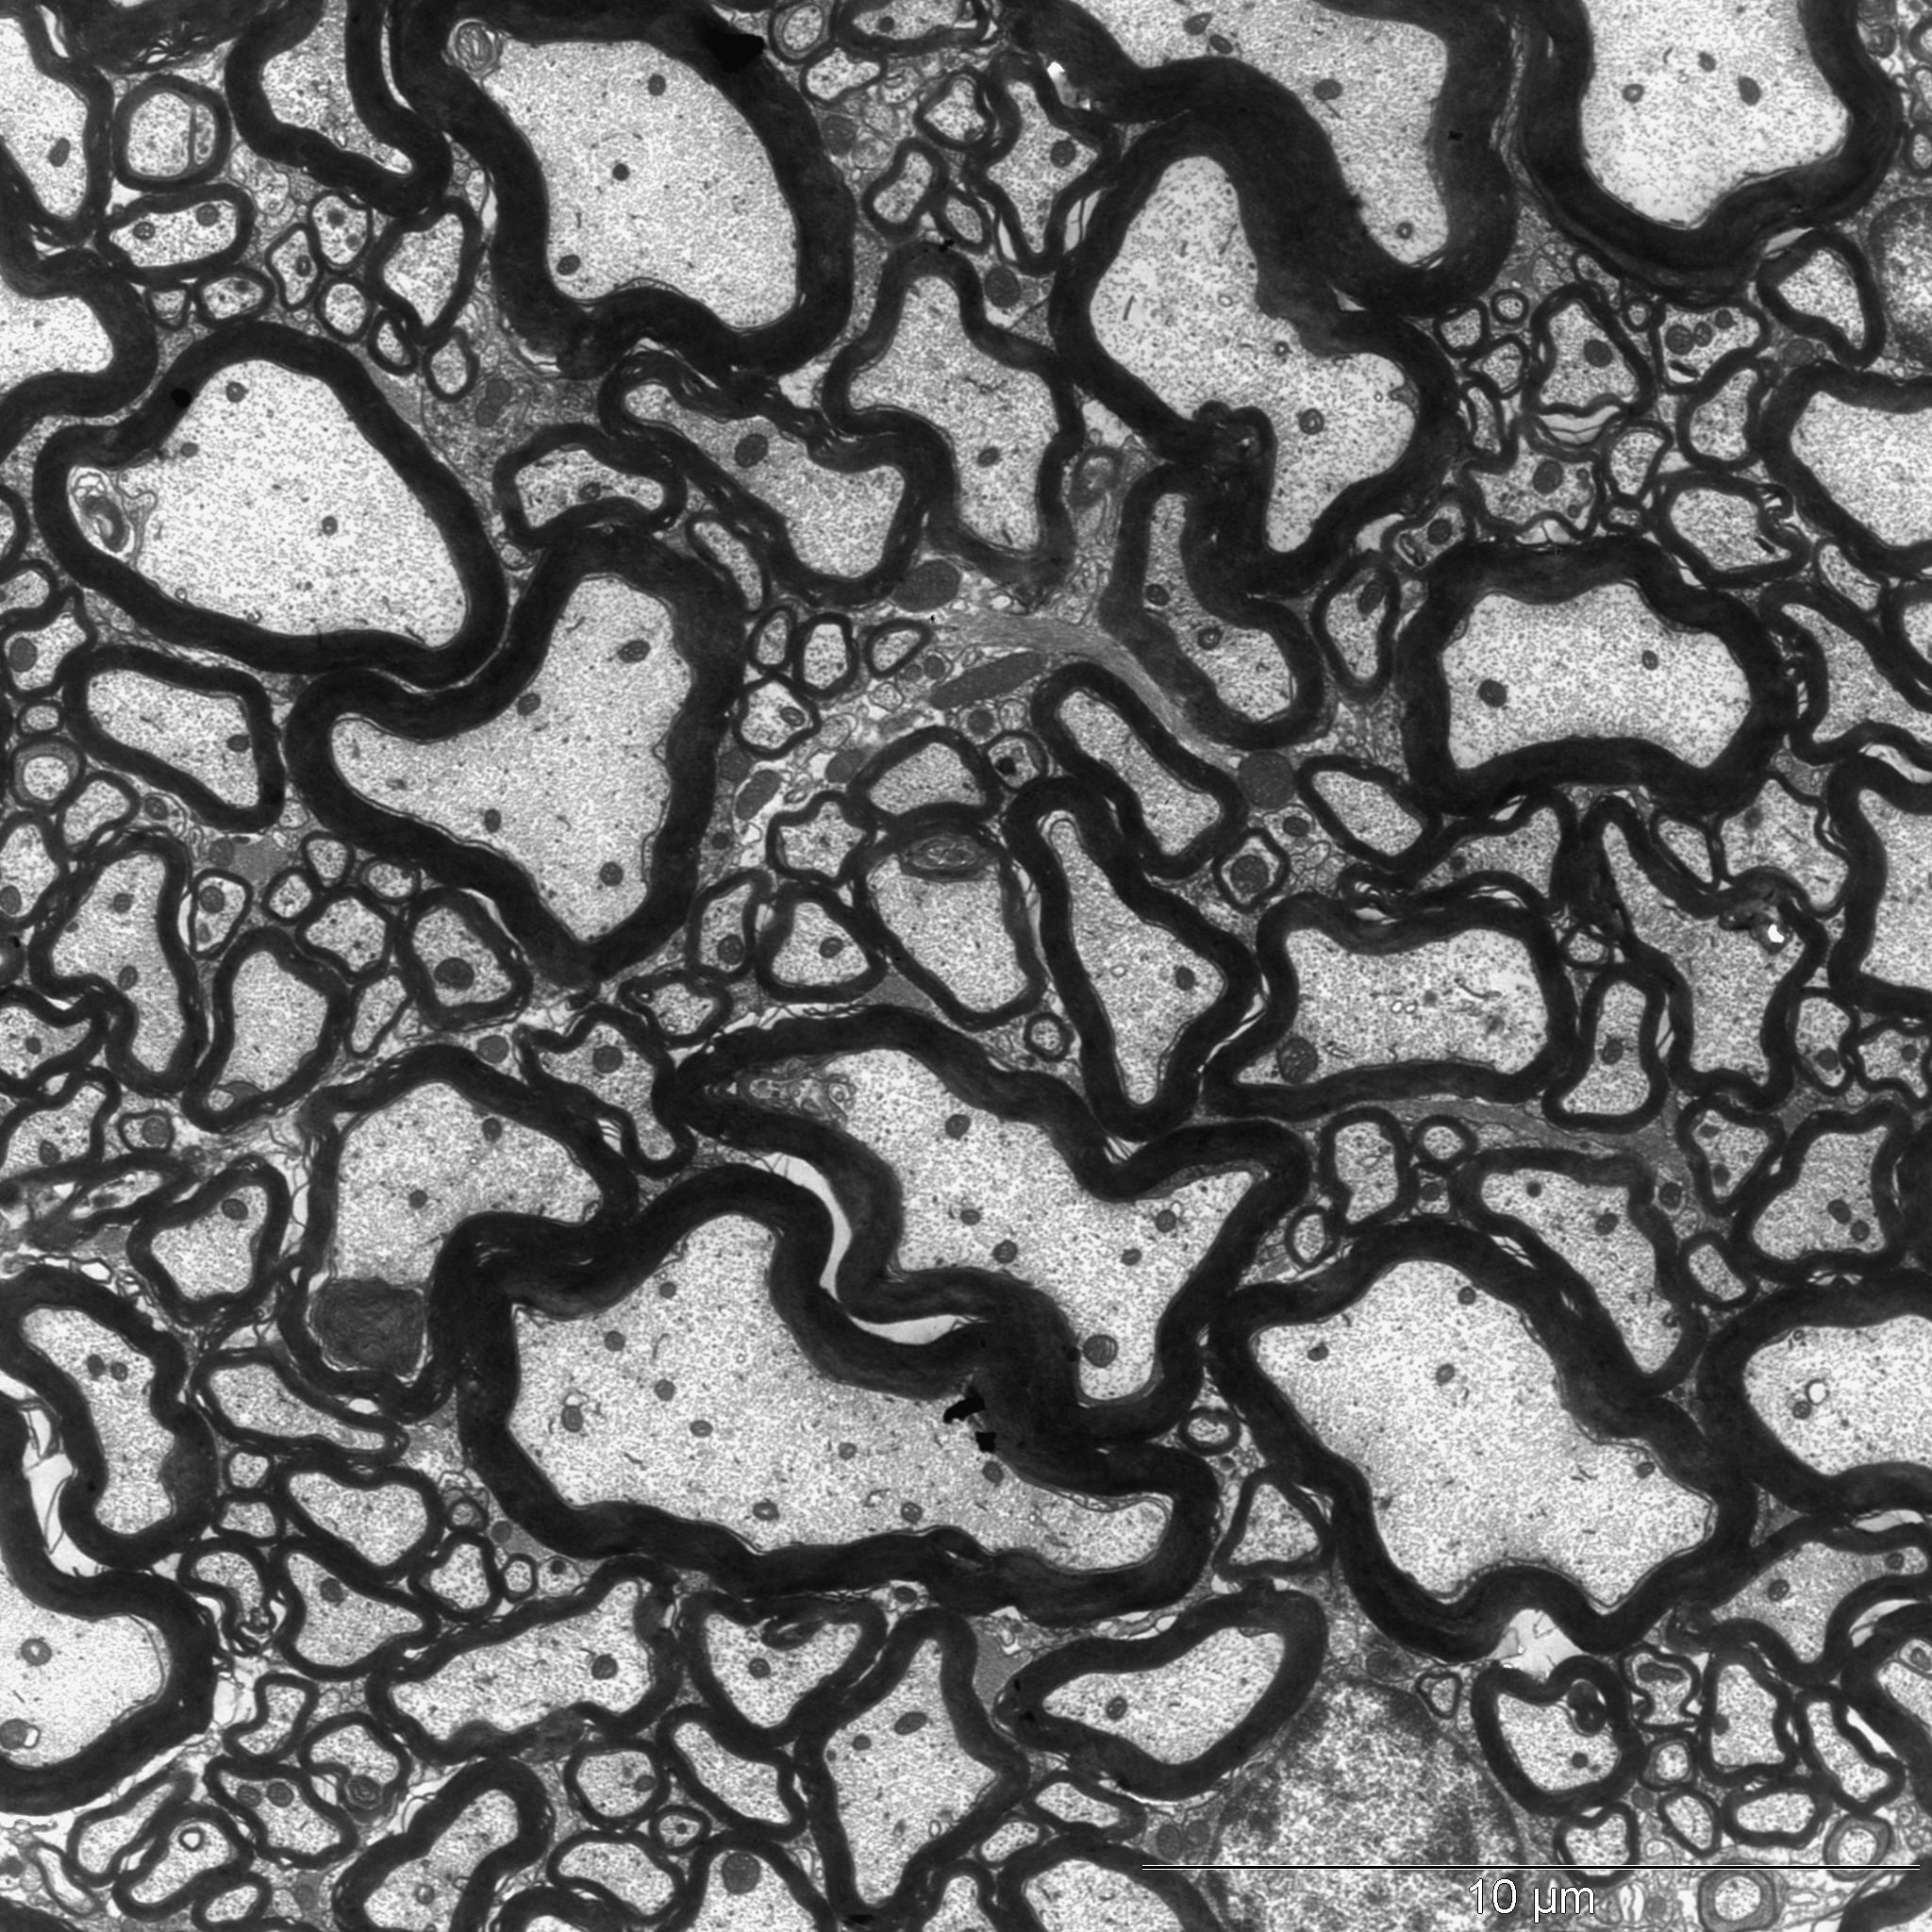

Tatsächlich wurden die Forschenden fündig: Wenn sie den Tieren den Kuhmilch-Inhaltsstoff Casein zusammen mit einem Wirkverstärker verabreichten, entwickelten die Mäuse danach neurologische Störungen. Unter dem Elektronenmikroskop zeigte sich, dass bei ihnen die Isolierschicht um die Nervenfasern geschädigt war, das Myelin. Die fettähnliche Substanz verhindert Kurzschlüsse und beschleunigt zusätzlich erheblich die Reiz-Weiterleitung.

Durchlöcherte Myelinschicht

Bei Multipler Sklerose zerstört das körpereigene Immunsystem die Myelin-Ummantelung. Die Folgen reichen von Missempfindungen über Probleme beim Sehen bis hin zu Bewegungs-Störungen. Im Extremfall enden die Betroffenen im Rollstuhl. Auch in den Mäusen war die isolierende Hülle massiv durchlöchert - offensichtlich ausgelöst durch die Casein-Gabe. „Als Grund vermuteten wir ähnlich wie in MS-Kranken eine fehlgeleitete Immunreaktion“, erklärt Rittika Chunder, die in der Arbeitsgruppe von Prof. Kürten habilitiert. „Die körpereigene Abwehr attackiert eigentlich das Casein, zerstört dabei aber auch Proteine, die an der Bildung des Myelins beteiligt sind.“